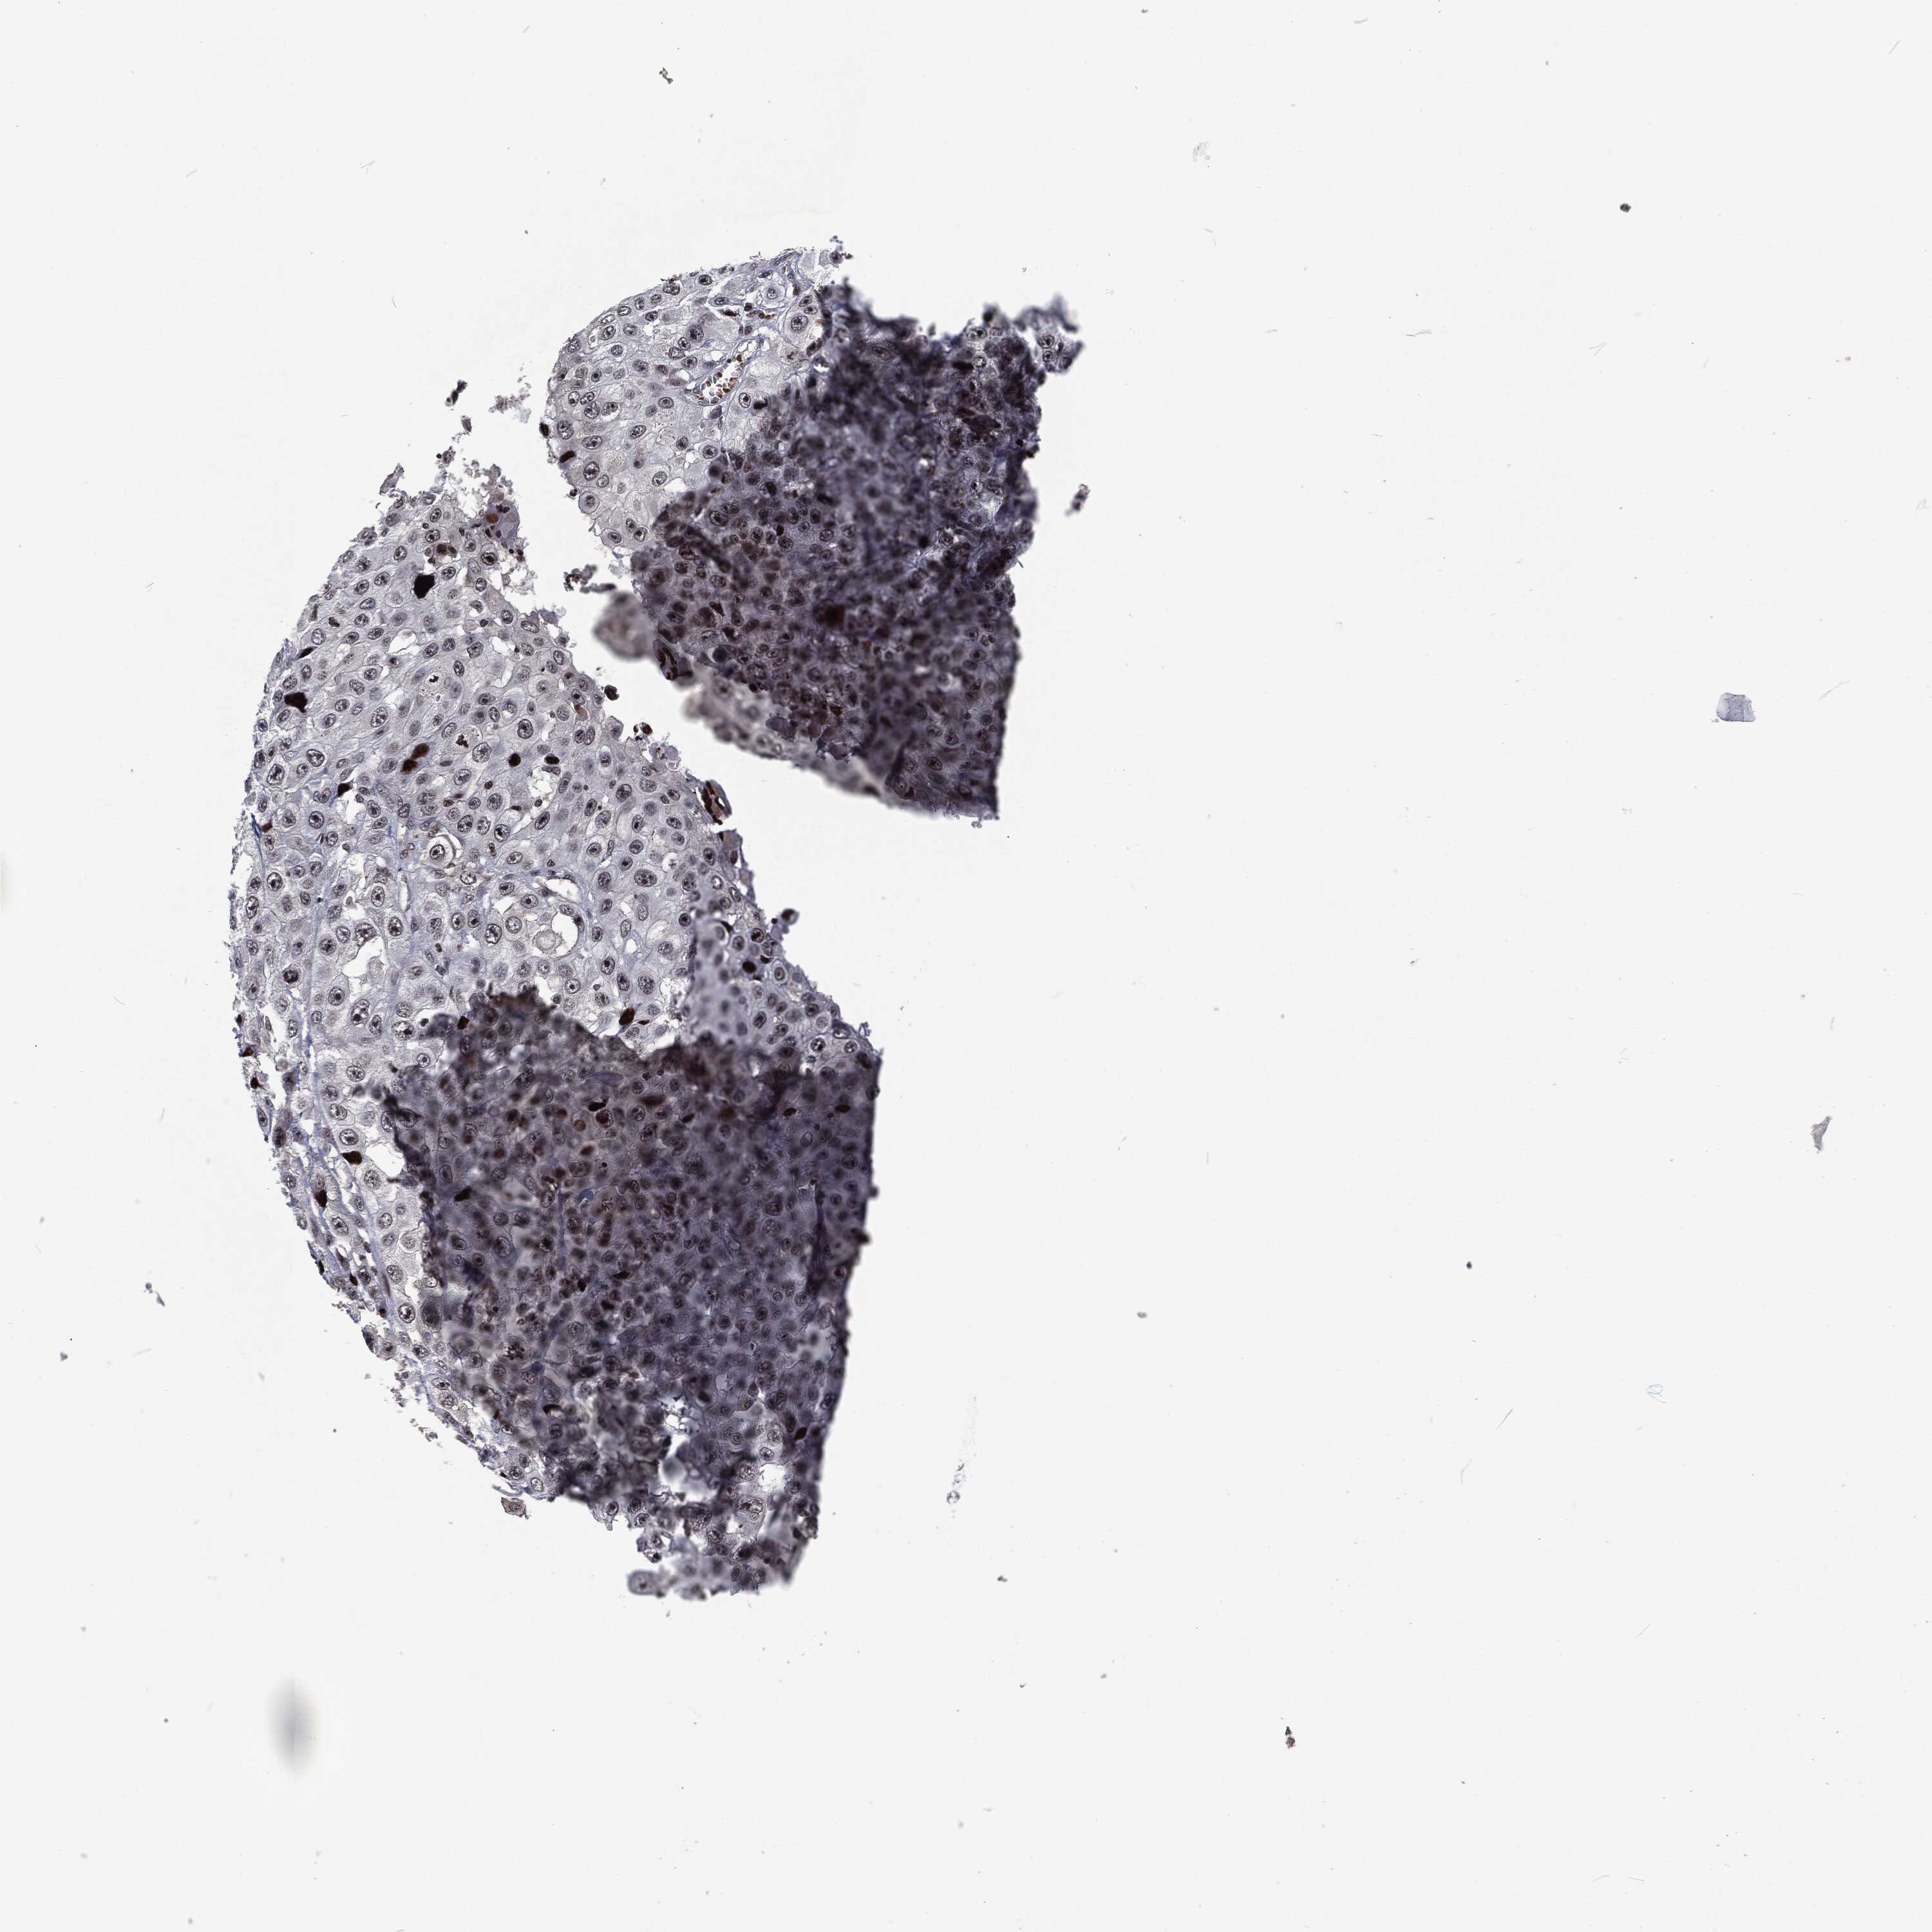

SKIN CANCER - Protein expressioni

A mouse-over function shows sample information and annotation data. Click on an image to view it in a full screen mode. Samples can be filtered based on level of antibody staining by selecting one or several of the following categories: high, medium, low and not detected. The assay and annotation is described here.

Each image is clickable and will lead to virtual microscopy that enables deeper exploration of all samples and also displays staining intensity scores, fraction scores and subcellular localization as well as patient and tissue information for each sample.

HPA001200

Staining

High

Medium

Low

Not detected

Squamous cell carcinoma, NOS

Basal cell carcinoma

Squamous cell carcinoma in situ, NOS

Squamous cell carcinoma, metastatic, NOS